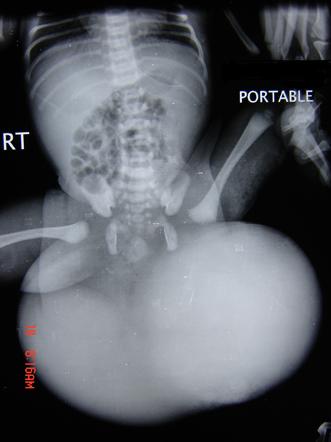

الورم المسخي العجزي العصعصي هو ورم يتطور قبل الولادة وينمو من العصعص عند الطفل ، وهو عظم الذنب.

يوجد هذا الورم في الفتيات أكثر من الأولاد ، ويحدث في حالة واحدة من كل 35000 ولادة.

كانت في الأسبوع 23 و 5 أيام من الحمل عندما أجرى كاس جراحة الجنين الطارئة. بحلول هذا الوقت ، كان الورم أكبر من الجنين تقريبًا.

Similar type of fetal tumor .